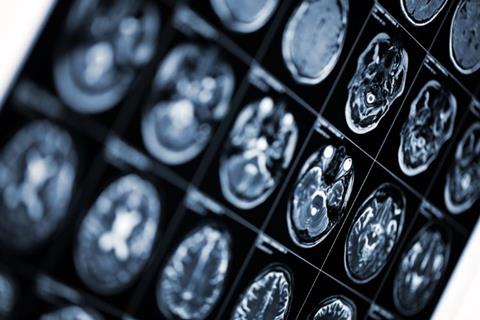

For both OCREVUS subcutaneous injection and OCREVUS IV infusion, most patients had no T1 gadolinium-enhancing (T1-Gd+) lesions, and no new/enlarging T2 lesions, at 24 weeks, the data found.